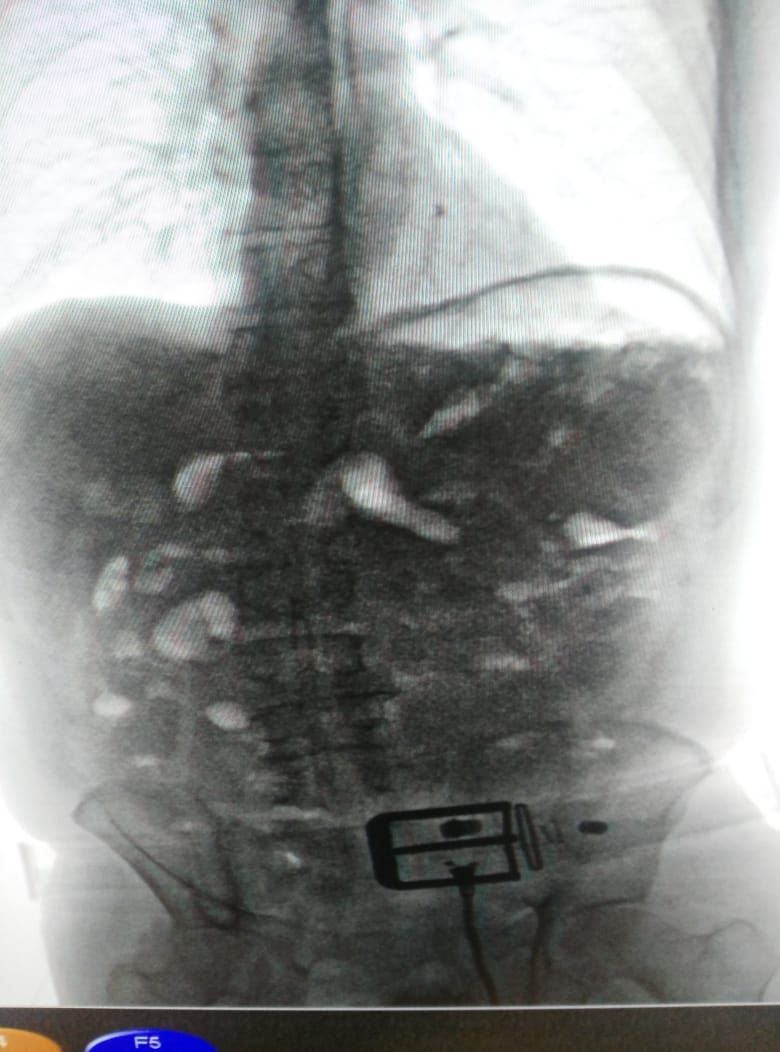

El ciudadano fue conducido hasta la sala de rayos x donde pasó voluntariamente por el Body Scan, las imágenes en las pantallas determinaban que en el abdomen habían cuerpos extraños en forma de dediles, un total de 87 piezas fueron contadas por el analista, después de hacerle conocer los derechos del capturado, entró en llanto, la preocupación que le embargaba se debía más a la necesidad de evacuar la sustancia del abdomen que a su judicialización.

El procedimiento adelantado en este tipo de eventos obligó al traslado a un centro asistencial autorizado para iniciar los protocolos médicos para extraer hasta el último dedil alojado dentro del estómago.